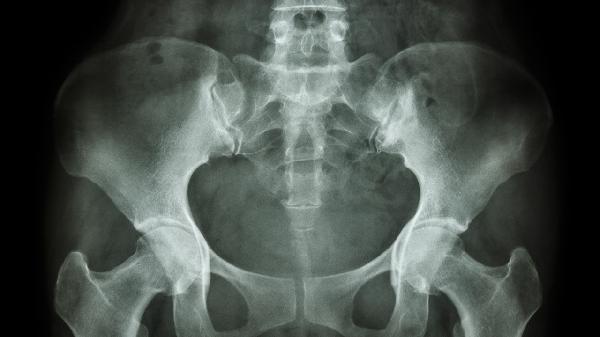

骨盆由髋骨、骶骨和尾骨三部分构成,是连接脊柱与下肢的重要骨性结构。

髋骨由髂骨、坐骨和耻骨在青春期后融合而成,形成骨盆的前外侧壁。髂骨上缘为髂嵴,是重要的体表标志;坐骨构成骨盆下部的坐骨结节;耻骨联合处有纤维软骨连接,妊娠期可适度松弛。髋骨与骶骨通过骶髂关节形成稳固连接,参与承重和运动功能。

骶骨由5块骶椎融合形成倒三角形骨块,上接腰椎下连尾骨。骶骨前后面分别有4对骶前孔和骶后孔,内有骶神经通过。骶骨两侧耳状面与髂骨构成骶髂关节,其稳定性由强韧的骶髂韧带维持。骶骨中央的骶管是椎管延续部分,容纳马尾神经。

尾骨由3-5块退化的尾椎融合构成,通过骶尾关节与骶骨相连。尾骨前侧面有尾骨肌附着,参与盆底肌群构成。女性尾骨较男性更向后倾斜,分娩时可向后移位扩大产道。尾骨损伤可能导致慢性尾骨痛,影响坐姿稳定性。